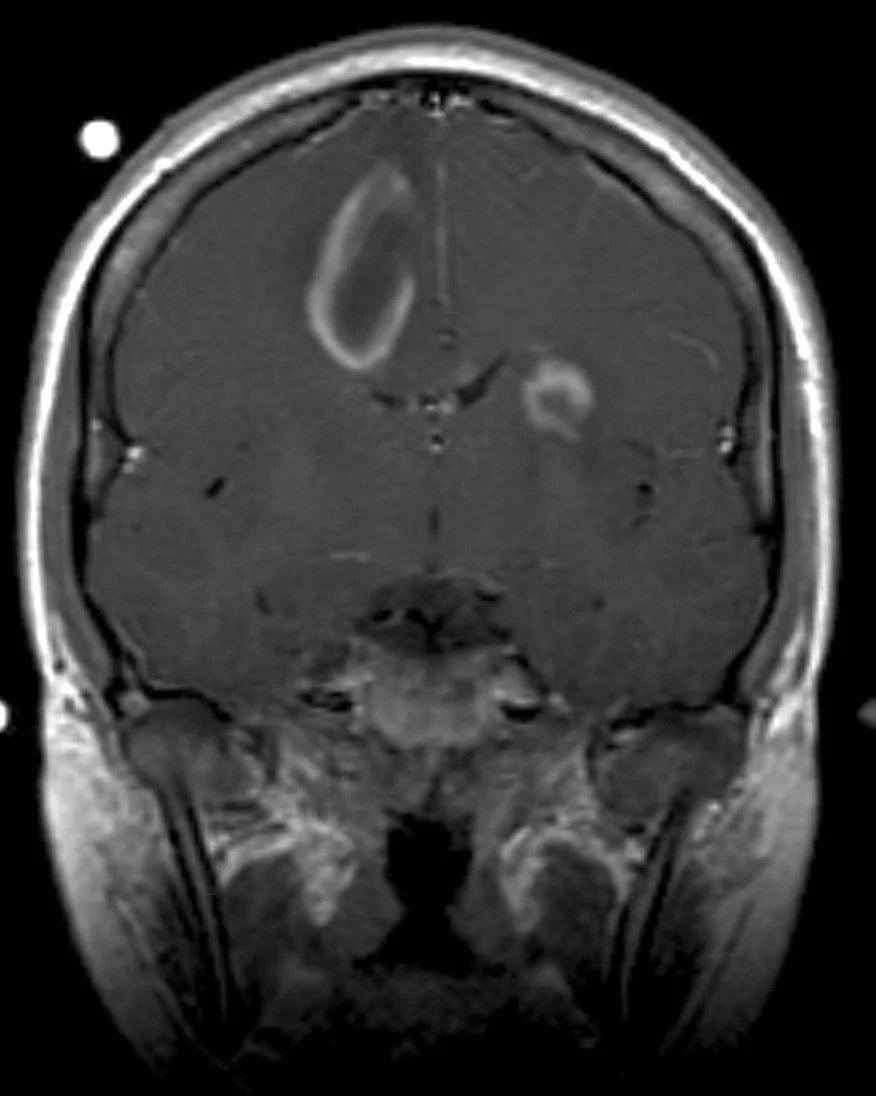

Open ring sign

DWI showing peripheral restriction without central restriction